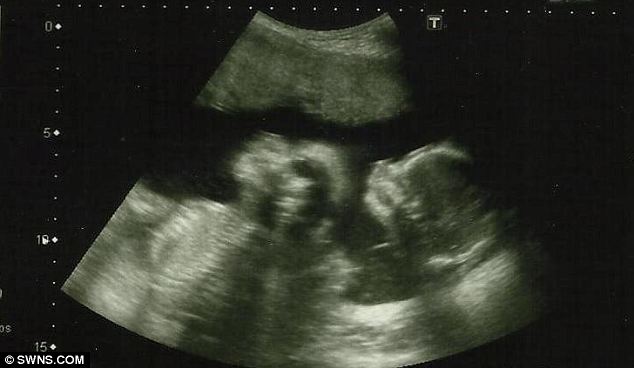

கொரோனா வைரஸ் தொற்று காரணமாக கம்பளை வைத்தியசாலையில் சிகிச்சை பெற்று வந்த ஐந்து மாத கர்ப்பிணிப் பெண்ணின் ஐந்து மாத சிசுவும் கொரோனா வைரஸ் தொற்று காரணமாக உயிரிழந்துள்ளதாக கம்பளை வைத்தியசாலையின் சுகாதார பிரிவு தெரிவித்துள்ளது.

இதன்போது, அந்த கர்ப்பிணிப் பெண்ணின் வயிற்றில் இருந்த சிசு உயிரிழந்துள்ளதாகவும் சத்திர சிகிச்சை மூலம் சிசு அகற்றப்பட்டதாகவும் வைத்தியர்கள் தெரிவித்தனர்.